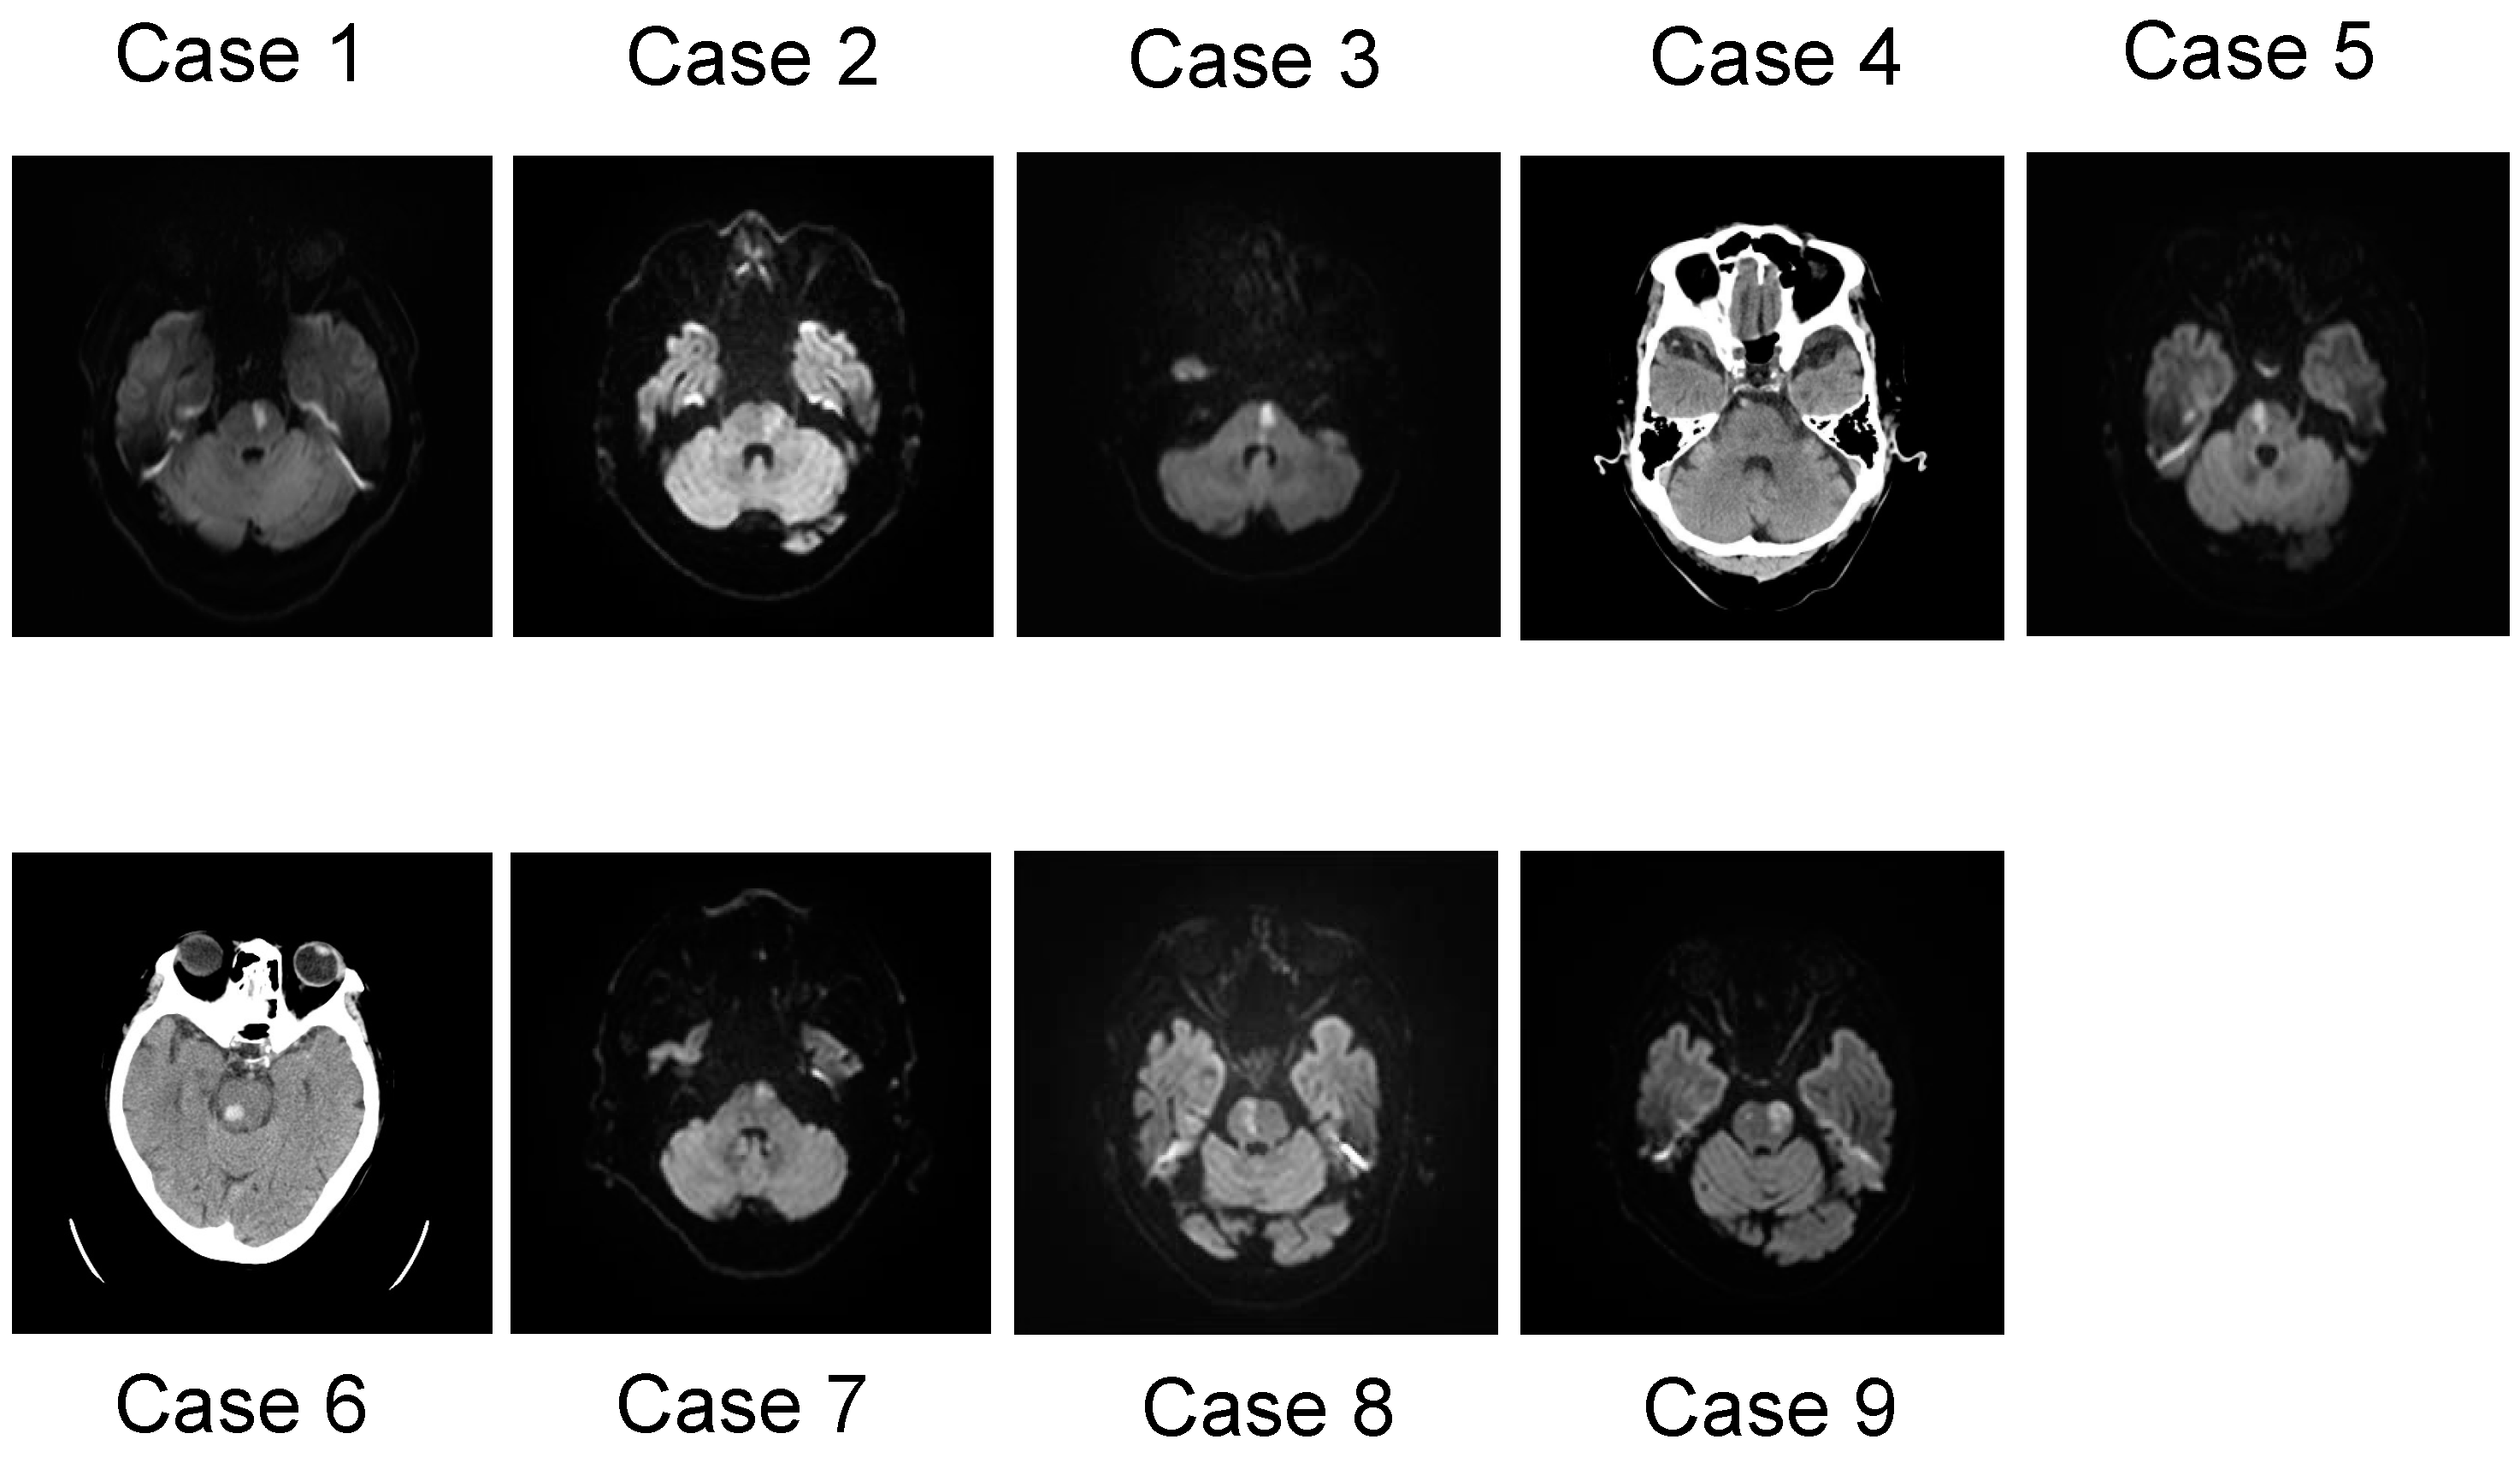

2.1. Case 1

2.2. Case 2

2.3. Case 3

2.4. Case 4

2.5. Case 5

2.6. Case 6

2.7. Case 7

2.8. Case 8

2.9. Case 9